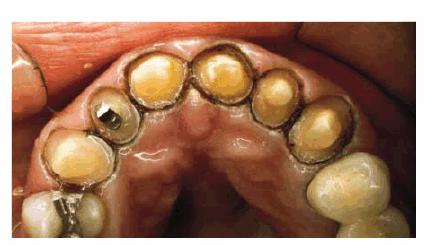

TREATMENT: When teeth are as crowded as this, it is sometimes necessary

to do a vital pulp extirpation to prepare the teeth for adequate porcelain

thickness. Thus, tooth preparation and diagnostic wax-up were first completed

on the study casts (Figures 24-7C, and 24-7D). The patient was fully informed of the possibility of

endodontic therapy. The actual tooth preparation can be seen in Figures 24-7E, and 24-7F. Fortunately, the pulp had receded, so extirpation was

not necessary. Electrosurgery was completed prior to impressions to improve

access to the preparation margins. Six full porcelain crowns restored the

esthetics of the maxillary arch (Figure 24-7G), whereas composite resin bonding helped restore

mandibular esthetics. A maxillary occlusal night appliance was constructed for

the patient to wear since the patient had a history of clenching while

sleeping.

Figure 24-7C: Diagnostic casts show the extent of crowding in the maxillary anterior teeth.

Figure 24-7D: A wax-up was completed to demonstrate to the patient and dental team how crowns could be used to accomplish the esthetic goal.

Figure 24-7E: Although the patient was warned that endodontic therapy might be necessary on the maxillary incisors, the teeth were prepared without pulpal exposures.

Figure 24-7F: The occlusal view shows the patient ready for impressions after electrosurgery for effective tissue displacement.